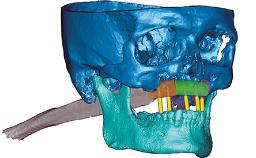

Rehabilitating an Edentulous Maxilla with a Conventional Removable Denture and an Edentulous Mandible with a Fixed Dental Prosthesis Using s-CAIS

This case describes a partial digital workflow in the treatment of a patient with a terminal dentition. It features virtual planning of static computer-aided implant surgery (s-CAIS) and CAD/CAM interim prostheses.

A 72-year-old male patient was referred to the prosthodontic clinic for possible implant treatment. He presented with a partially edentulous maxilla and mandible. The clinical and radiographic examination showed generalized chronic severe periodontitis with tooth mobility, dental caries, and direct composite restorations in three teeth. Pre-treatment periapical and panoramic radiographs revealed horizontal bone loss associated with all remaining teeth and vertical bone loss associated with the anterior teeth and confirmed the presence of generalized carious lesions.